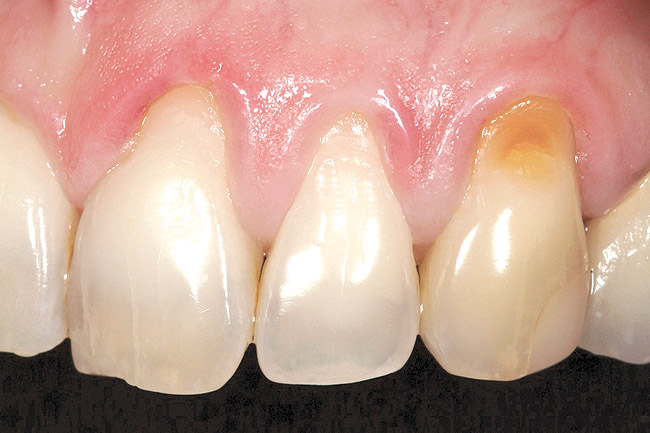

The 2.5-week postoperative clinical view can be seen in Figure 10 through Figure 12. Note the rapid soft tissue healing and maturation. At 6-weeks postoperative, tissue plasty was accomplished to blend the thickened keratinized tissue, in addition to placement of class V composite restorations at teeth Nos. 5, 6, and 11 to create a new restorative margin on the root surfaces.

The 2-month postoperative view can be seen in Figure 13 through 15. Note the color match of the tissue, balance of the facial heights of contour, and zones of attached keratinized tissue present.

Figure 13  Case One The 2-month postoperative view, maxillary right.

Figure 13

Figure 14  Case One The 2-month postoperative view, maxillary anterior.

Figure 14

Figure 15  Case One The 2-month postoperative view, maxillary left

Figure 15